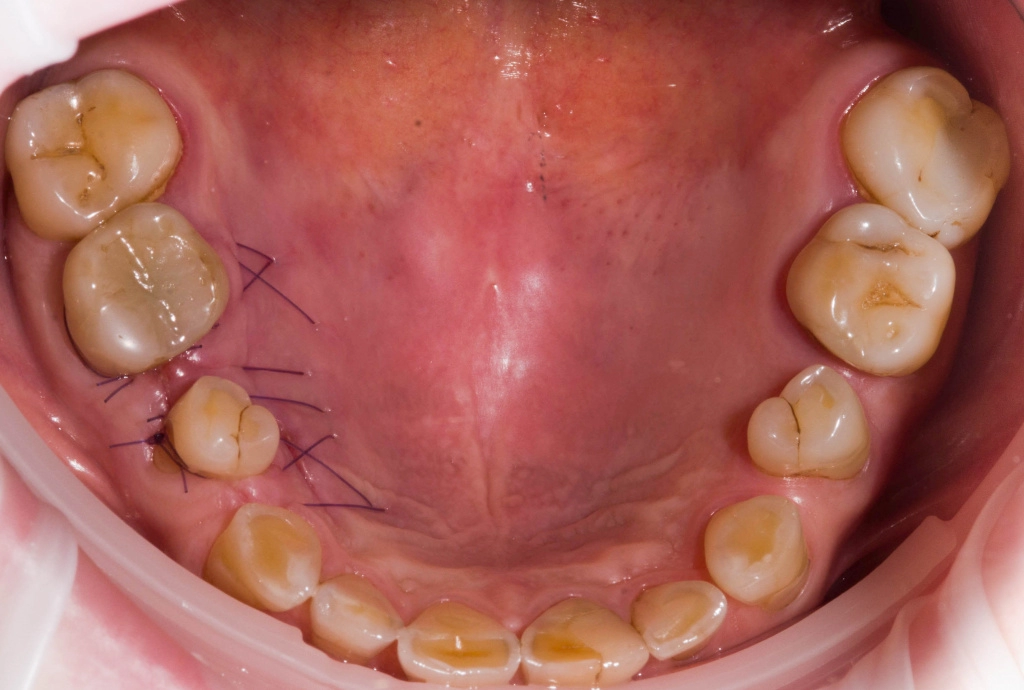

Удалены корни 3.6, 4.6, с одномоментной установкой имплантатов 3.6, 4.6 и забором соединительно-тканного трансплантата с небной поверхности в области 1.6.